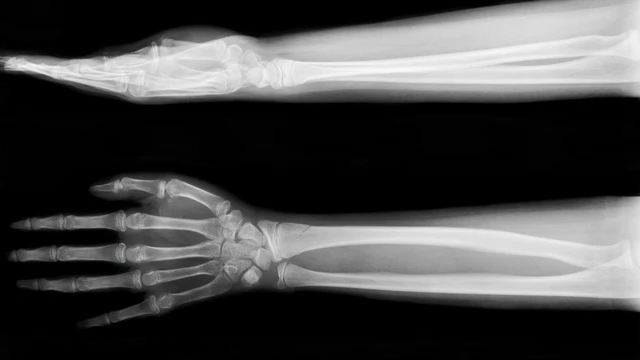

/https://cms-prod.s3-sgn09.fptcloud.com/chup_x_quang_xuong_cang_tay_thang_nghieng_la_ky_thuat_gi_chi_dinh_va_quy_trinh_1_db0a02d43d.png)

Cẳng tay, bộ phận nối liền giữa khớp cổ tay và khớp khuỷu tay, đóng vai trò quan trọng trong cử động linh hoạt của bàn tay. Tuy nhiên, cấu trúc phức tạp bên trong cẳng tay tiềm ẩn nhiều nguy cơ tổn thương mà mắt thường khó có thể quan sát. Do đó, chụp X-quang xương cẳng tay trở thành "cánh tay đắc lực" cho y khoa trong việc chẩn đoán và điều trị hiệu quả các bệnh lý liên quan. Bài viết dưới đây sẽ giúp bạn hiểu rõ hơn về kỹ thuật chụp X-quang xương cẳng tay thẳng nghiêng.